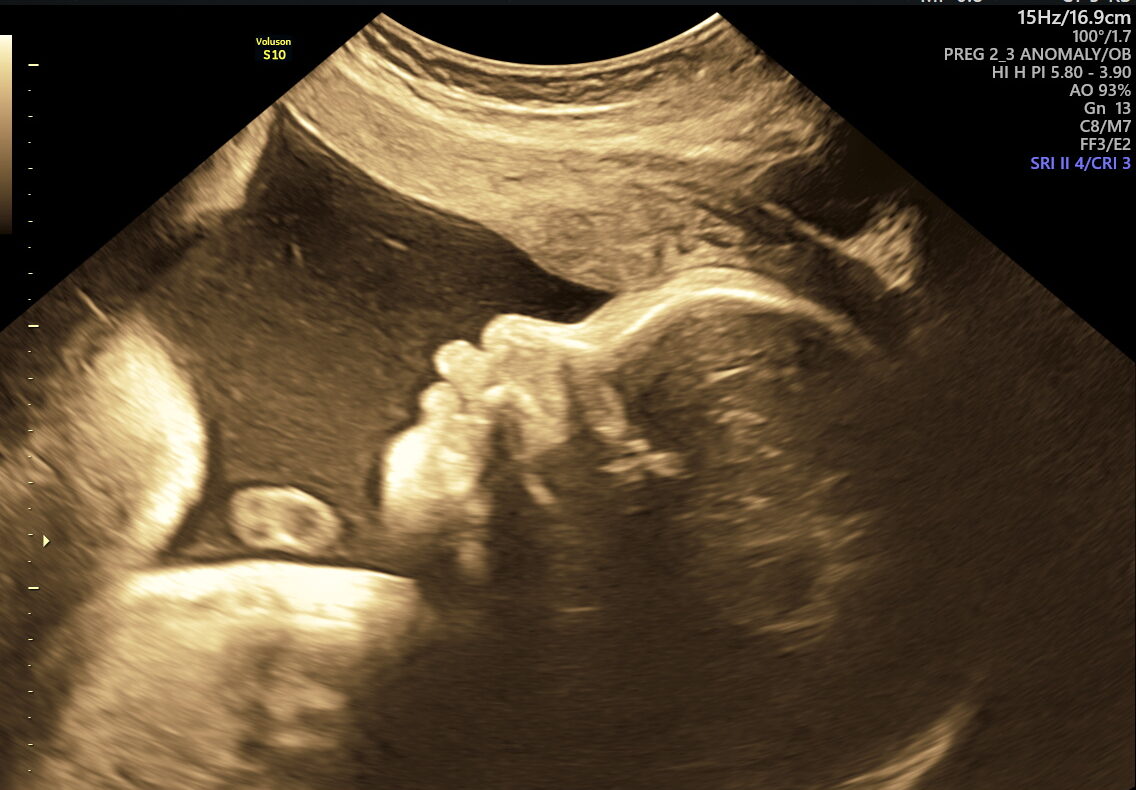

As your pregnancy journey enters its final weeks, NESA Institute of Fetal Medicine offers the Fetal Well-being Scan—a specialized ultrasound performed between 28 and 40 weeks. This essential check ensures your baby’s health and readiness for birth, giving you and your family confidence and clarity as you approach delivery.

- Birth Preparation: Confirms the baby’s position (head-down, breech, transverse) and checks readiness for labour.

- Vital Functions: Measures movements, breathing, and heart rate to make sure your baby is thriving.

This scan focuses on confirming birth readiness and spotting sudden issues that may arise close to your due date. It includes detailed Doppler studies to check blood flow in the umbilical cord and brain, ensuring your baby gets enough oxygen and nutrients.

- Abnormal umbilical cord blood flow or cord entanglement